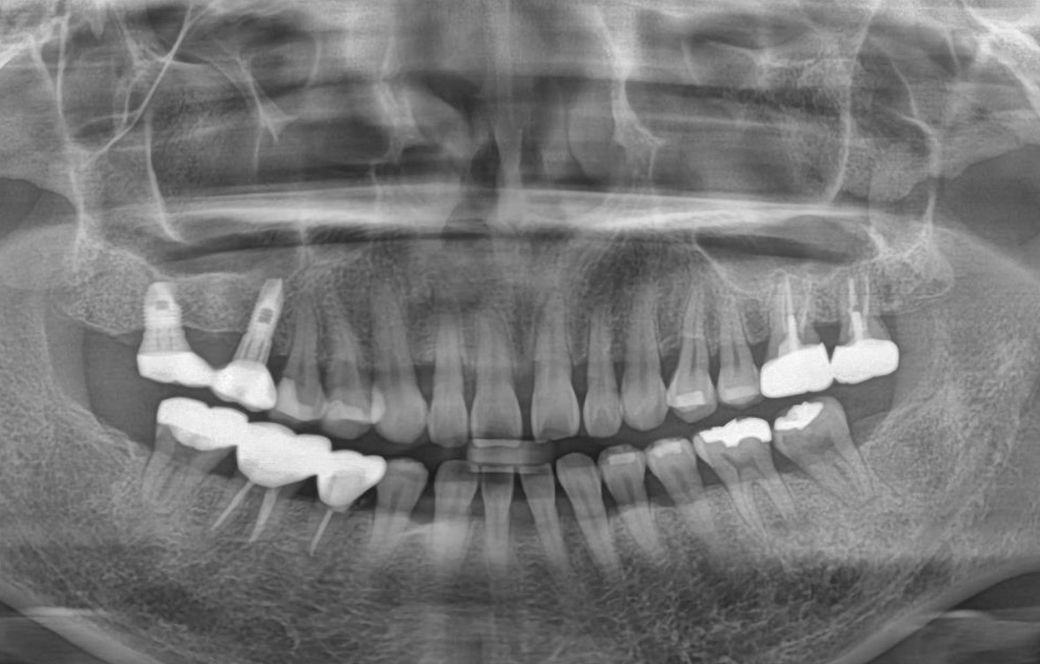

25년 11월 엑스레이 입니다.

사진상 왼쪽 신경치료된 어금니가

저작시는 괜찮은데 옆으로 뉴르면 미세하게

아파요.

위로 누르면 안아파요

치과를 가봐도 신경치료 잘됐고(2-3년됨)

큰 이상 없대는데 ㅠㅠ

• 2번 째 사진

사진상으로는 크게 문제가 보이지는 않습니다만 계속 불편하다면 재신경치료 해야할 수 있습니다.

잔존 신경이 약간 남아있다면 그럴 수 있습니다 재신경치료를 해볼 수 있습니다 좀 더 신경관을 확대해서 세척해보는 겁니다

사진으로는 치아에 특별한 문제가 없어 보입니다. 치아에 통증이 있는 원인은 여러가지가 있을수 있습니다 외부로 보이는 이상이 없음에도 불구하구 불편감이 있다면 치아에 금이 갔거나 했을수 있습니다. 치아에 금이 간 경우에는발치를 해야하는 상황이 발생할수도 있습니다.